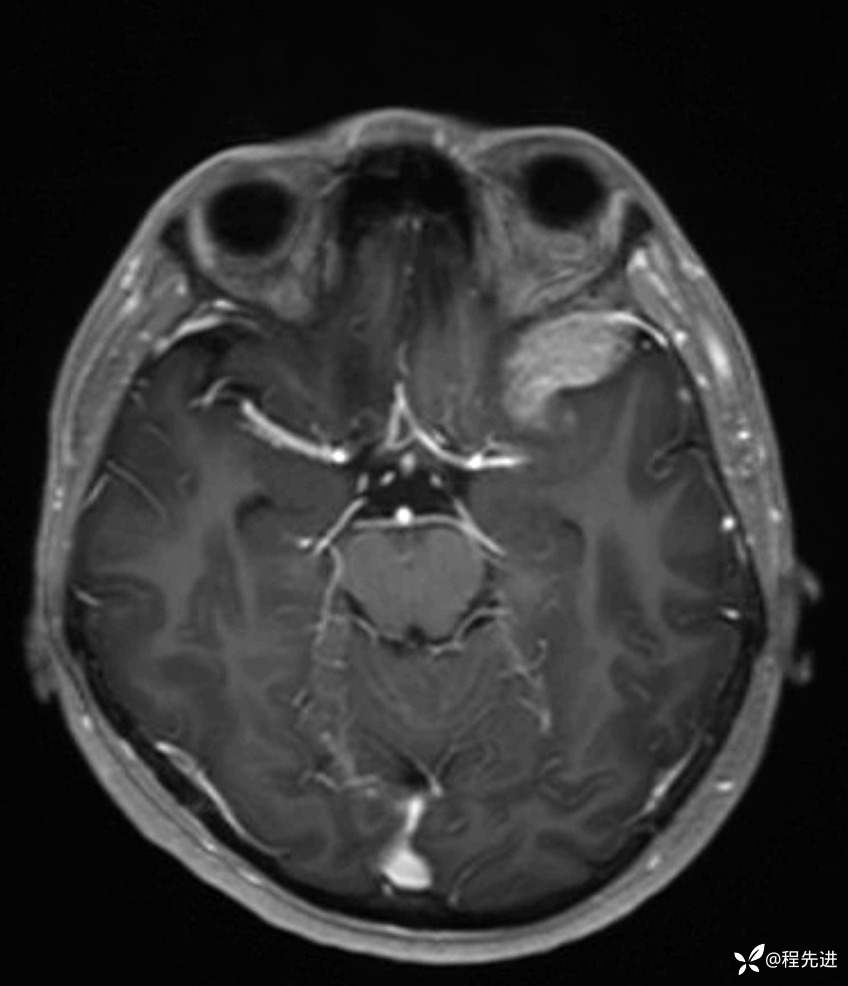

MR平扫+增强:

FLAIR: